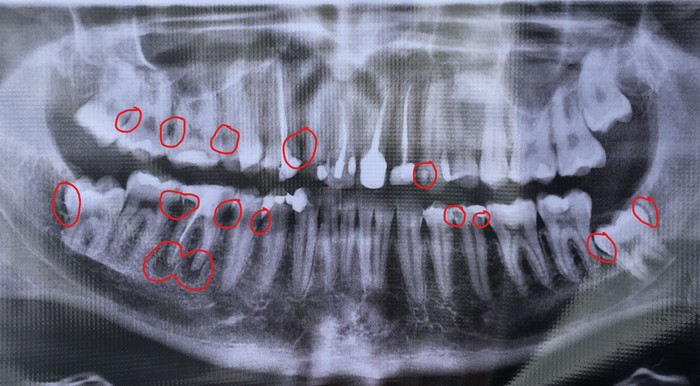

Примерно вот так:

Местный горе-врач по непонятной причине тупо выдрал всё что увидел гнилого, не попытавшись сохранить корни. Из-за этого остальные зубы "поплыли", что в будущем сыграло свою негативную роль.

Всё начинается с неё. Обязательной частью составления плана лечения является – тщательная диагностика. В нашем случае, она будет заключаться в сборе анамнеза – врач обязан уточнить, по какому поводу и с какой проблемой явился пациент (плановый ли это осмотр или причиной стало наличие болевых ощущений, или дискомфорта), провести осмотр непосредственно в полости рта, заглянув в самые сокровенные участки вашего тела и, наконец, рентген обследование. Без рентгена сейчас никуда. Я бы даже советовал, на первичный приём сразу приходить со свежим, да простят меня пикабушники, ортопантомограммным (рис.4) снимком (свежим считается снимок, которому не более полугода), так как это сильно облегчит постановку диагноза, сохранит время вам и врачу и, что самое важное, может показать наличие скрытых полостей или скрытых патологических процессов (рис.4 обведенные участки) - это как правило кариозные процессы или локализованные гингивиты\пародонтиты, которых не видно невооруженным глазом. Чаще всего – это участки в области межзубных промежутков и, всё те же участки на боковых поверхностях крайних жевательных зубов.